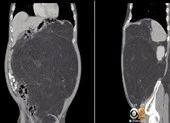

Sau khi thăm khám, các bác sĩ chẩn đoán anh S. bị u xơ thần kinh, phải chụp cộng hưởng từ. Nhưng khi chụp, khối u quá lớn làm anh S. không thể vào được lồng chụp nên các bác sĩ không phân biệt được đâu là u, đâu là dây thần kinh.